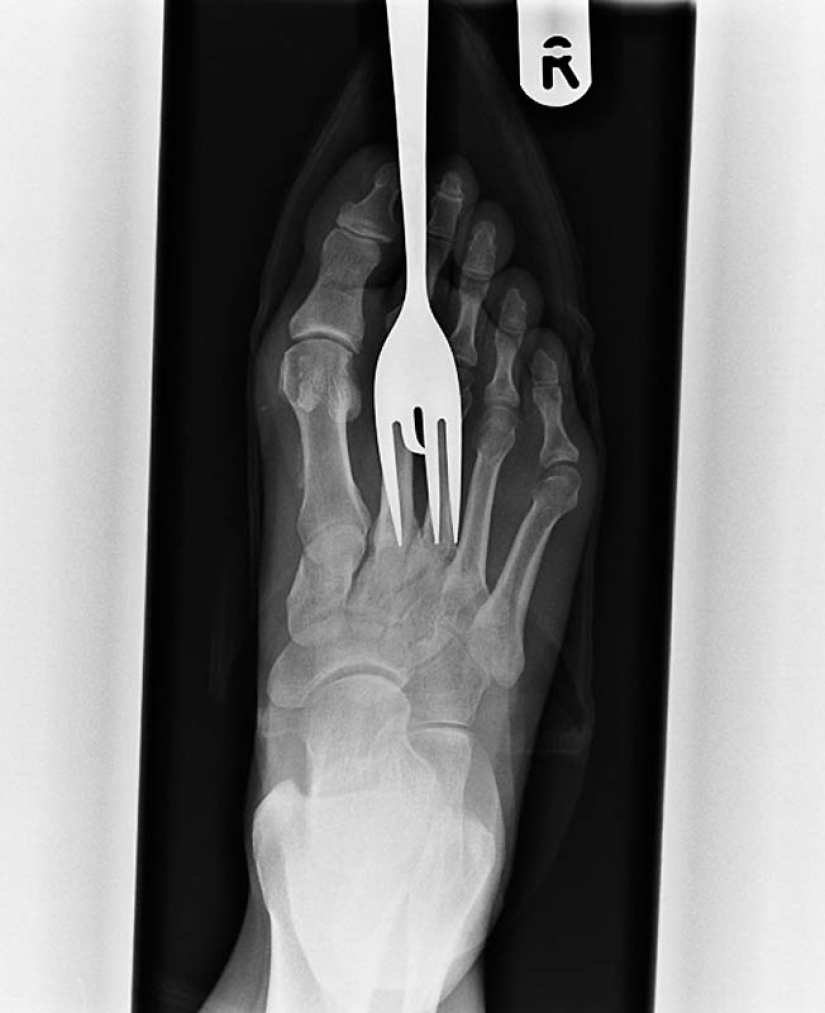

7. X-ray of the patient who stepped on the fork.

10. Another patient who stepped on a fork.